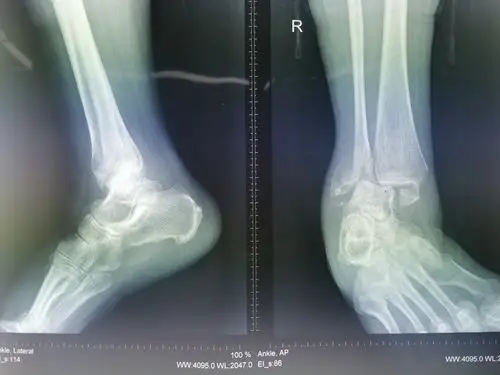

如此艰辛历程旋前外旋型踝关节骨折

踝关节骨折.楼梯湿滑导致踝关节旋前~外旋四度损伤,下胫腓分离 - 抖音

旋后外旋3度踝关节骨折,后77外固定